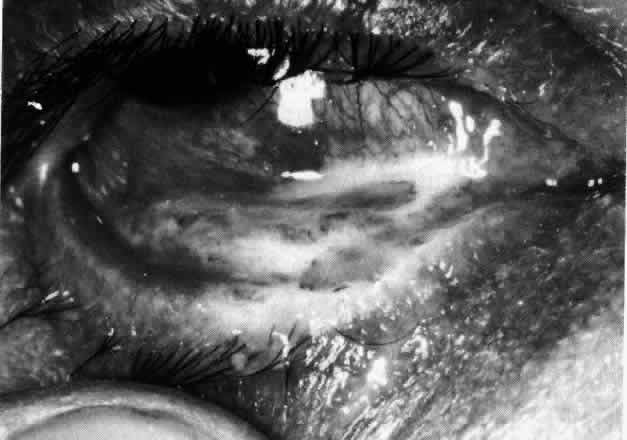

Simple and nodular episcleritis differ in their clinical courses, but in both the edema and infiltration are entirely within the episcleral tissues. The sclera is not involved. The maximum congestion is in the superficial episcleral network, with some slight congestion of the conjunctival vessels and deep episcleral vessels (Fig. 10). The intraocular structures are not involved in either variety, nor is the visual acuity affected. Anterior segment fluorescein angiography reveals a normal vascular pattern but a very rapid flow rate, with the whole transit of the dye being completed within 2 or 3 seconds (Figs. 11 and 12).

Fig. 11. Anterior segment fluorescein angiogram of a 45-year-old woman with simple episcleritis. At first transit of dye, all the vessels are dilated and filling simultaneously. However, the vascular pattern is not disturbed.

Fig. 12. Angiogram of the same 45-year-old woman in Figure 11 one second later. Within 1 second, all the vessels are filled and there is even, venular filling except in the deep episcleral plexus. This is the rapid filling pattern seen in all forms of episcleritis and in diffuse anterior scleritis.